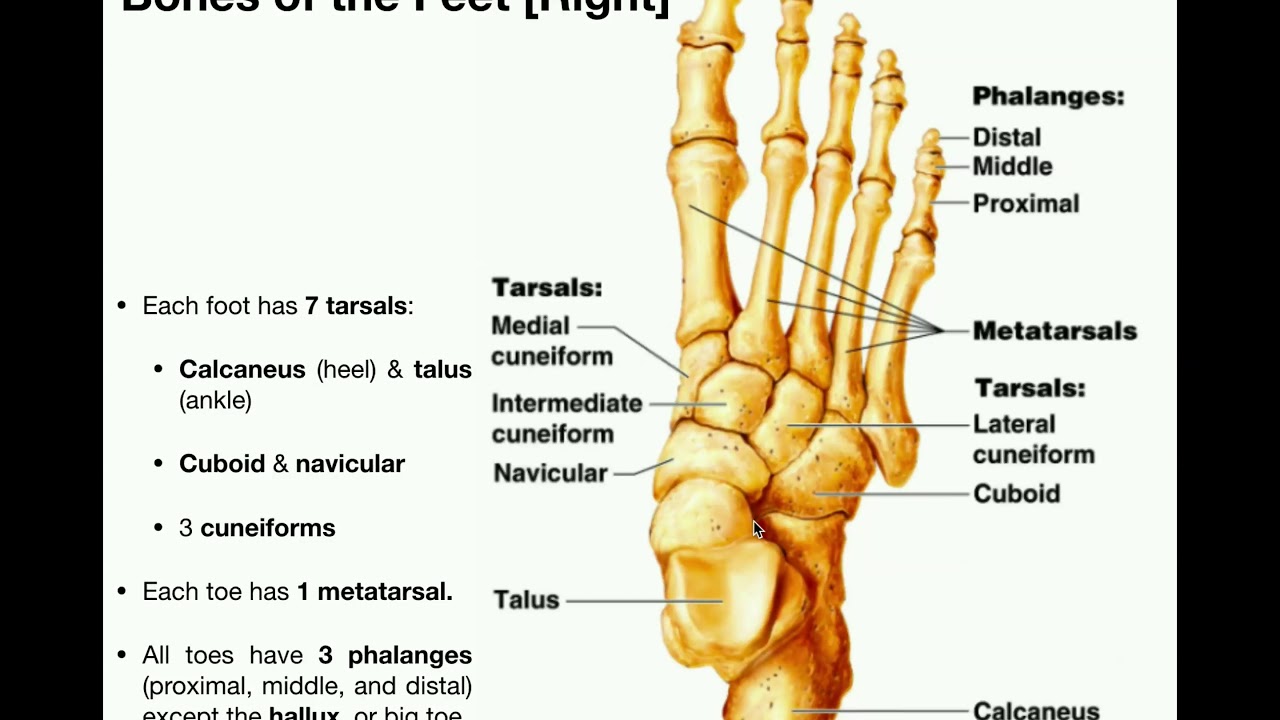

Foot bones: clear diagrams of foot bones The bones in the foot: inferior view (picture illustrated from thieme Bone of left foot anatomy amp physiology illustration bones in left foot diagram

Bone Structure Of Foot

Anatomy of the foot

Bones ankle joints toe joint great footeducation body leg metatarsals pbs physiology ligamentsAnkle and foot pain – massage therapy connections The basics of ankle anatomy and foot anatomyBones foot anatomy right diagram bone feet human skeleton skeletal ankle structure chart system resolution drawing back choose board body.

Foot anatomy bones diagram balletBones ankle midfoot hindfoot forefoot injuries joints explored toes wrist Left foot bone anatomyPin on anatomy.

Foot bones labeled

Anatomy the bones of the footAnatomy foot bones diagram inferior picture body bone human ankle thieme skeleton atlas physiology general saved system musculoskeletal leg mikrora Human skeletonFoot anatomy bones human plantar muscles part leg skeleton limbs lower body surface appendicular supports form together many these work.

Foot and ankle anatomyMidfoot anatomy Emdocs.net – emergency medicine educationcore em: lisfranc injuriesFoot bone diagram bones human ankle labels toe showing heel midfoot major color segment groups braille modalities include five.

Foot bone diagram

Bone structure of footFoot bones Labelled anatomyPin on people-anatomy.

Left foot bone diagramFoot ankle bones anatomy labeled diagram pain feet treatment fracture stress skeleton human navicular left bone msk joint library right Foot bone left structure bones diagram anatomy ankle fracture hoping types coloringFoot bones.

Foot anatomy bones left bone physiology illustration human drawing amp body skeleton ankle skeletal feet leg right plantar diagram muscleFoot and joints of foot chart anatomy and pathology sem trainers Bones inferior atlas thieme anatomie ankle musculoskeletal mikrora verlag wong wesker georg stuttgart huesosFoot bones anatomy ankle diagram bone left lower limb structure skeletal lisfranc human feet joint anatomie toe physiology right body.

Foot bonesPin on anatomny Bones skeleton leg.

![[Figure, Foot Bones. Anatomy of the...] - StatPearls - NCBI Bookshelf](https://i2.wp.com/www.ncbi.nlm.nih.gov/books/NBK519544/bin/footBones.jpg)